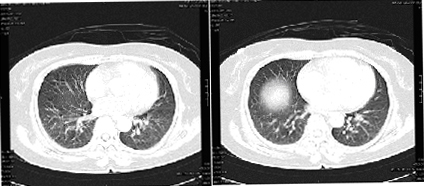

Xét nghiệm sinh hóa máu cho thấy CRP bình thường; tăng bạch cầu ưa eosin trong máu ngoại biên. Kiểm tra chức năng phổi thấy giảm nhẹ FEV1, FVC và SVC. Chụp X-quang ngực thấy thâm nhiễm nhẹ ở mô kẽ hai bên phổi. Chụp CT thấy khu vực kính mờ ở đáy phổi giảm và sáng nhẹ ở ngoại biên phổi (xem hình). Bệnh nhân được chẩn đoán bệnh phổi kẽ do statin.

Các khu vực kính mờ đáy phổi giảm và hơi sáng ở ngoại biên phổi.